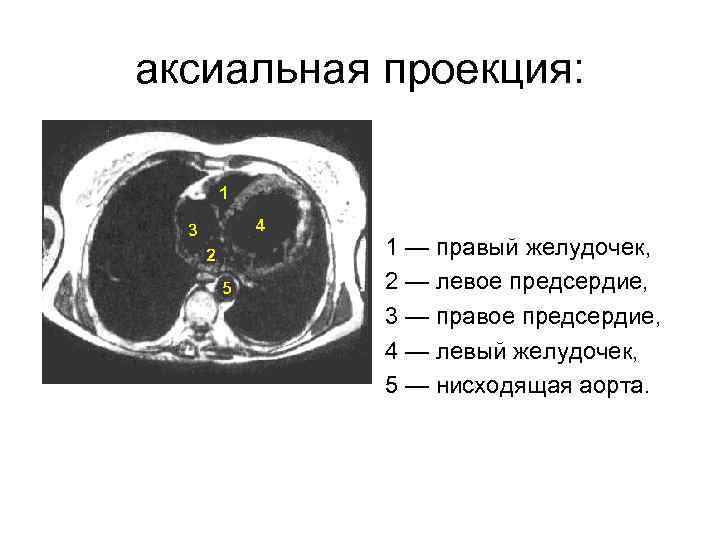

аксиальная проекция: 1 — правый желудочек, 2 — левое предсердие, 3 — правое предсердие, 4 — левый желудочек, 5 — нисходящая аорта.